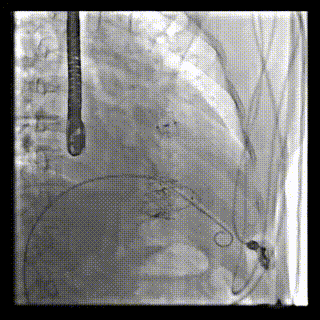

2021年12月24日,復(fù)旦大學(xué)附屬中山醫(yī)院葛均波院士團(tuán)隊成功應(yīng)用LuX-Valve Plus為一例極重度三尖瓣反流(TR)合并房顫、房缺的患者完成了經(jīng)血管三尖瓣置換術(shù),這是在前基礎(chǔ)上,本周完成的第三例經(jīng)血管三尖瓣置換手術(shù),葛均波院士、周達(dá)新教授等與心外科魏來教授、賴顥教授,心超室的潘翠珍教授、李偉教授及麻醉科的郭克芳教授共同完成了本周手術(shù),均獲得圓滿成功!患者術(shù)后超聲顯示無TR,臨床癥狀明顯改善。本周手術(shù)的成功也為LuX-Valve Plus救治性臨床研究添上了濃墨重彩的一筆。

本周三例接受LuX-Valve Plus經(jīng)血管三尖瓣置換術(shù)的患者中,第一例患者為冠狀動脈旁路移植術(shù)+Bentall+二尖瓣成形術(shù)后;第二例患者為永久起搏器植入術(shù)后,存在跨三尖瓣導(dǎo)線;第三例患者合并房顫、房缺及左心耳封堵術(shù)后。

三例患者入院后,葛均波院士團(tuán)隊周達(dá)新教授、潘文志教授、張源博士、陳莎莎博士及心超室的潘翠珍教授、李偉教授對患者的情況進(jìn)行詳細(xì)評估和討論,最終決定為三例患者選擇LuX-Valve Plus40mm、50mm和50mm型號的瓣膜進(jìn)行手術(shù)治療。手術(shù)后即刻拔除氣管插管,術(shù)后患者三尖瓣反流癥狀得到顯著改善,復(fù)查心超結(jié)果顯示人工三尖瓣瓣膜支架固定穩(wěn)定,瓣葉關(guān)閉形態(tài)未見異常,未見明顯反流。

LuX-Valve Plus是LuX-Valve系列產(chǎn)品的第二代,采用的是經(jīng)血管入路的全新輸送系統(tǒng),其設(shè)計開發(fā)過程得到了上海中山醫(yī)院葛均波院士及其團(tuán)隊的精心指導(dǎo),研究結(jié)果提示瓣膜植入的安全性和有效性俱佳,尤其瓣膜獨特的設(shè)計使其具有極佳自適應(yīng)性,本周三例患者病因及解剖結(jié)構(gòu)各具特點,但均可從LuX-Valve Plus植入術(shù)明顯獲益。目前,LuX-Valve Plus已在全國各中心開展救治性臨床研究,相信未來定會為更多的三尖瓣反流患者帶來福音。